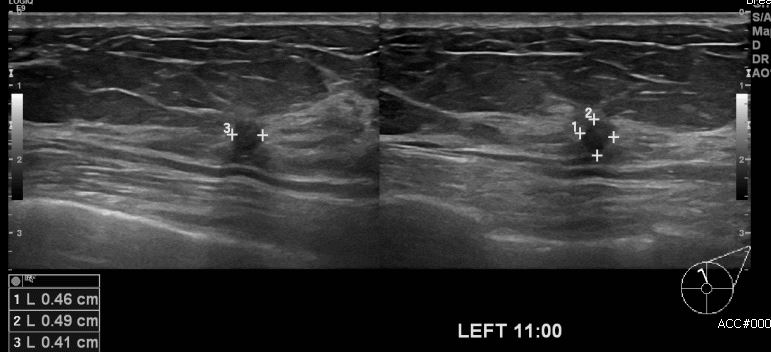

상기환자 건강검진상 이상소견으로 내원하신 70대 여성분으로 본원 초음파상 좌측

유방 11시 방향에 의심스러운 멍울 조직검사 시행하여 좌측 침윤성 유관암 진단 되었습니다.